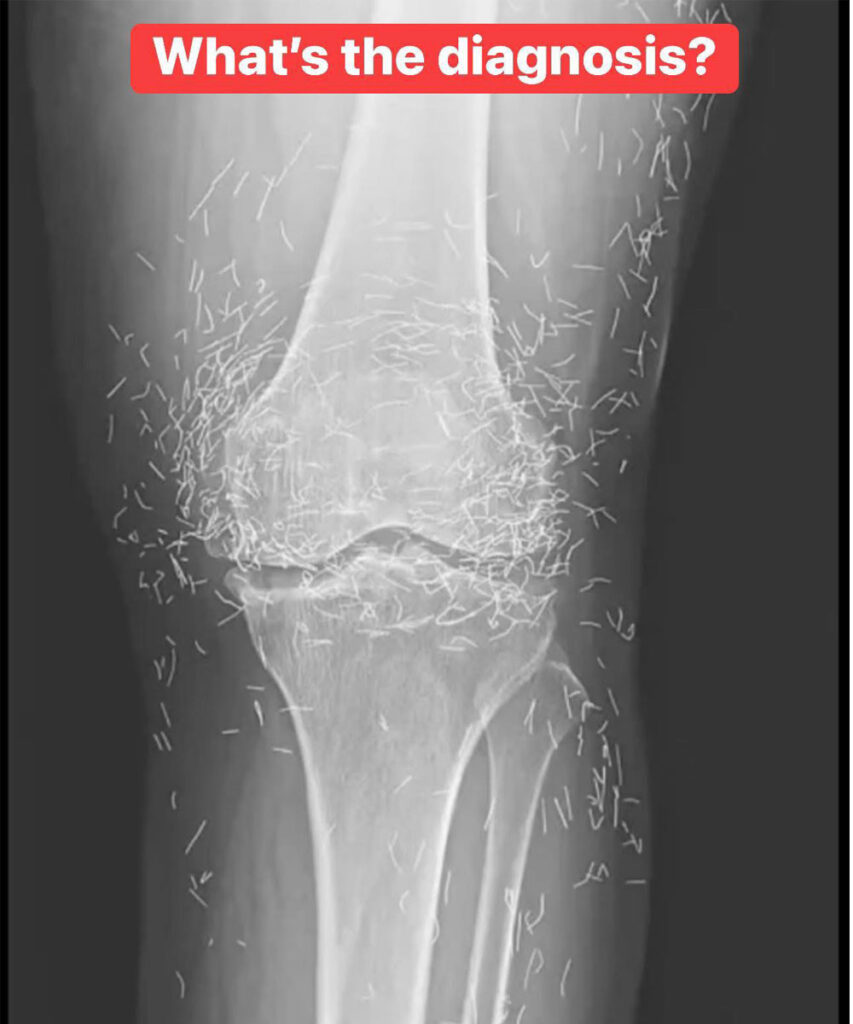

As doctors examined an X-ray image of the knees of an old woman experiencing severe joint pain, they found a gold mine: hundreds of tiny gold acupuncture needles left in her tissue.

In the woman’s acupuncture treatment, the needles, which were presumably made of gold, were intentionally left in her tissue for continued stimulation, the report says.

It could also make it hard for a doctor to read an X-ray. “The needles may obscure some of the anatomy,” Guermazi said.